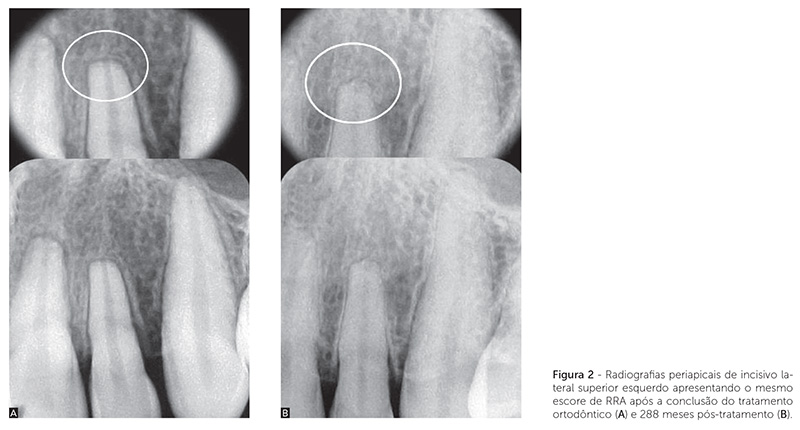

A Figura 2 mostra radiografias periapicais de um incisivo lateral maxilar, em que a RRA não alterou após a finalização do movimento ortodôntico em longo prazo. A Figura 3 mostra a diferença de detalhes de uma RRA em um incisivo central, por meio de TCFC e RP. A Figura 4 mostra a sobreposição de imagens, sugerindo RRA por meio de RP, enquanto a imagem de TCFC mostra ausência de RRA.

Evidenciou-se RRA em incisivo lateral superior sem alteração em longo prazo (Fig. 2); presença de RRA em incisivo central (Fig. 3) e ausência de RRA (Fig. 4) em pré-molar (superior), por meio de RP e de TCFC.

A frequência de RRA, após a conclusão do tratamento ortodôntico (T2) e decorridos 52 a 288 meses desse (T3), foi determinada por meio de imagens de RPs. As RRAs mais frequentes foram as de escore 1. Os dados não demonstraram diferença significativa entre T2 e T3 para nenhum dos escores (Tab. 1). Esses resultados mostraram-se similares aos de estudos anteriores9,10. Copland e Green9 verificaram, por meio de radiografias cefalométricas, se a RRA associada com tratamento ortodôntico progredia após o término do tratamento ativo. Os incisivos centrais superiores de 45 indivíduos foram avaliados após o término do tratamento, sendo que o tempo médio decorrido entre a conclusão do tratamento e a obtenção das radiografias finais foi de 2 anos e 4 meses (28 meses). Os resultados mostraram a paralização da RRA. Remington et al.10 avaliaram as reabsorções radiculares apicais em 100 pacientes por meio de RPs após a conclusão do tratamento ortodôntico e decorrido um período médio de 14,1 anos (169 meses). Os resultados sugeriram que, finalizado o tratamento, 52% dos dentes apresentaram escores 0 e 1. A avaliação em longo prazo não mostrou aumento na RRA após a remoção do aparelho, exceto remodelações de arestas e bordas afiadas, como também observado na amostra do presente estudo (Fig. 2).